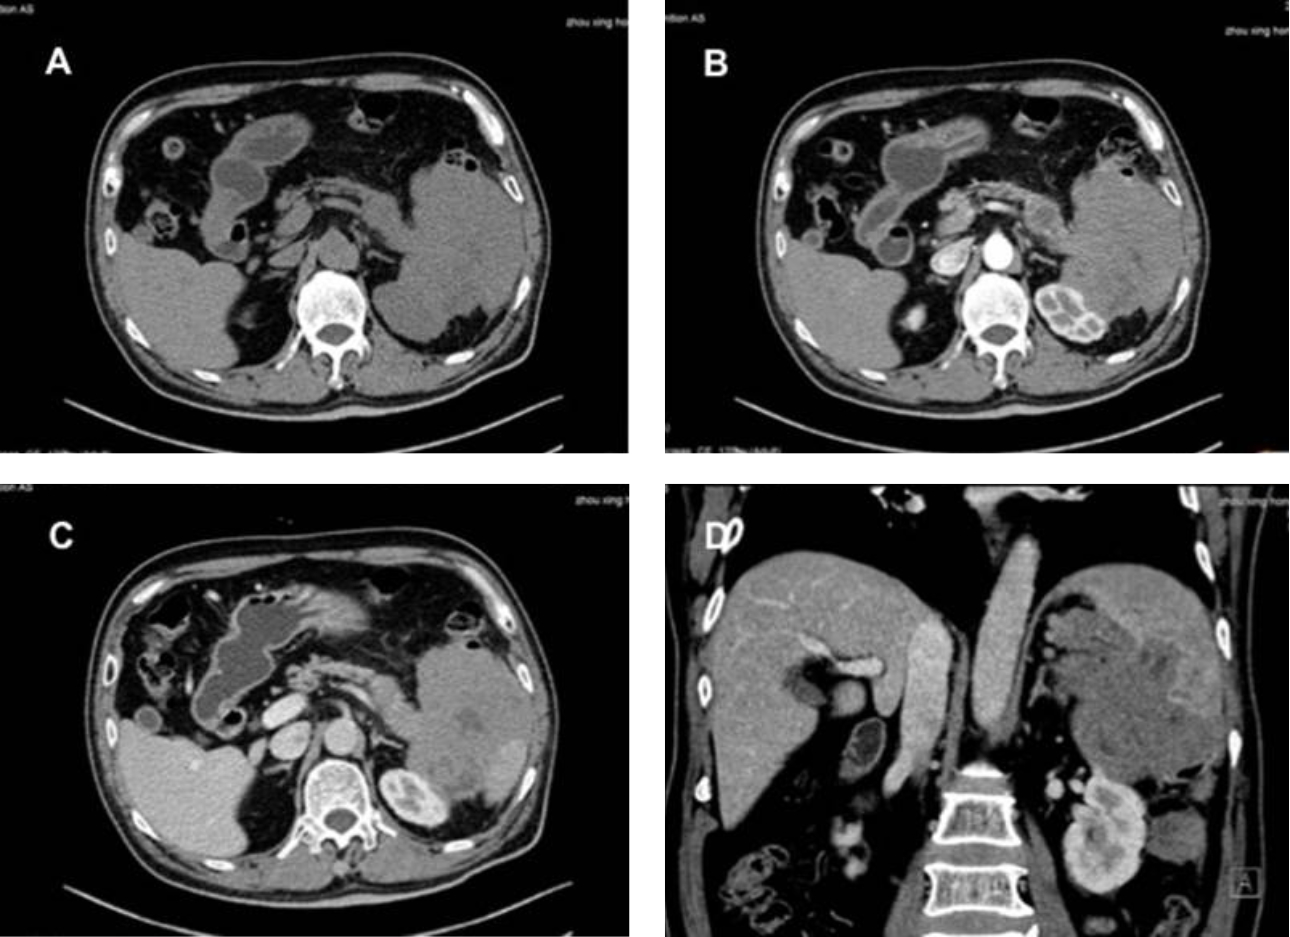

형상3: 전신 PET/CT에서 췌장꼬리(pancreatic tail), 비장, 좌측 신장, 비장 공간(splenorenal space), 비장 위 공간(splenogastric space)의 연조직 종괴(soft tissue masses )가 비정상적으로 증가한 포도당 대사와 함께 보여짐